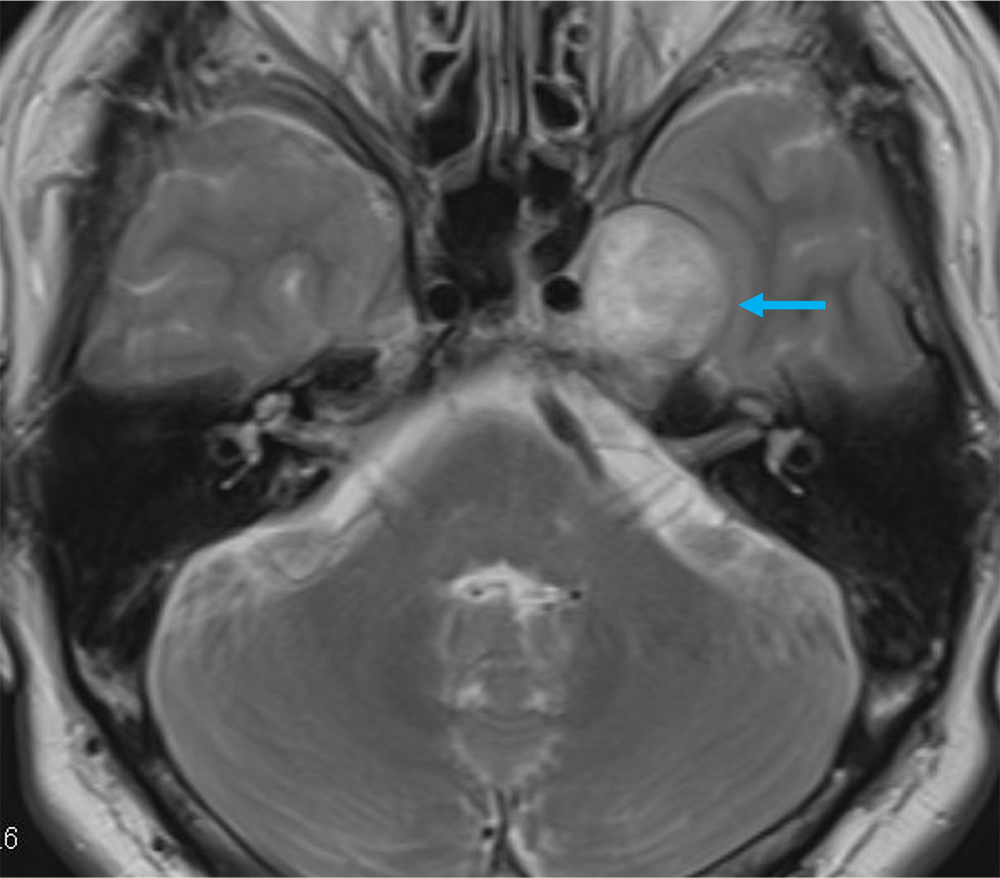

単純MRIのT2強調画像では左メッケル腔から背側に突出する腫瘍を認め、三叉神経鞘腫と髄膜腫が鑑別となる。Gd造影剤の脂肪抑制T1強調画像では腫瘍は全体に濃染し、冠状断では卵円孔を介した頭蓋外進展が見られ、三叉神経鞘腫の可能性が高い。内側では海綿静脈洞を圧排、背側では橋の軽度圧排も見られる。有症状であり、手術が施行され、三叉神経鞘腫と診断された。

三叉神経鞘腫を確実に診断するためには、神経走行に沿った進展を確認することである。Gd造影剤を用いた3Dの脂肪抑制T1強調画像を撮影することで、thin sliceの造影CTと同様に後から再構成したMPRを作成するにより、腫瘍の進展方向を確実に診断することが可能であり、本症例には必須のシーケンスと思われた。